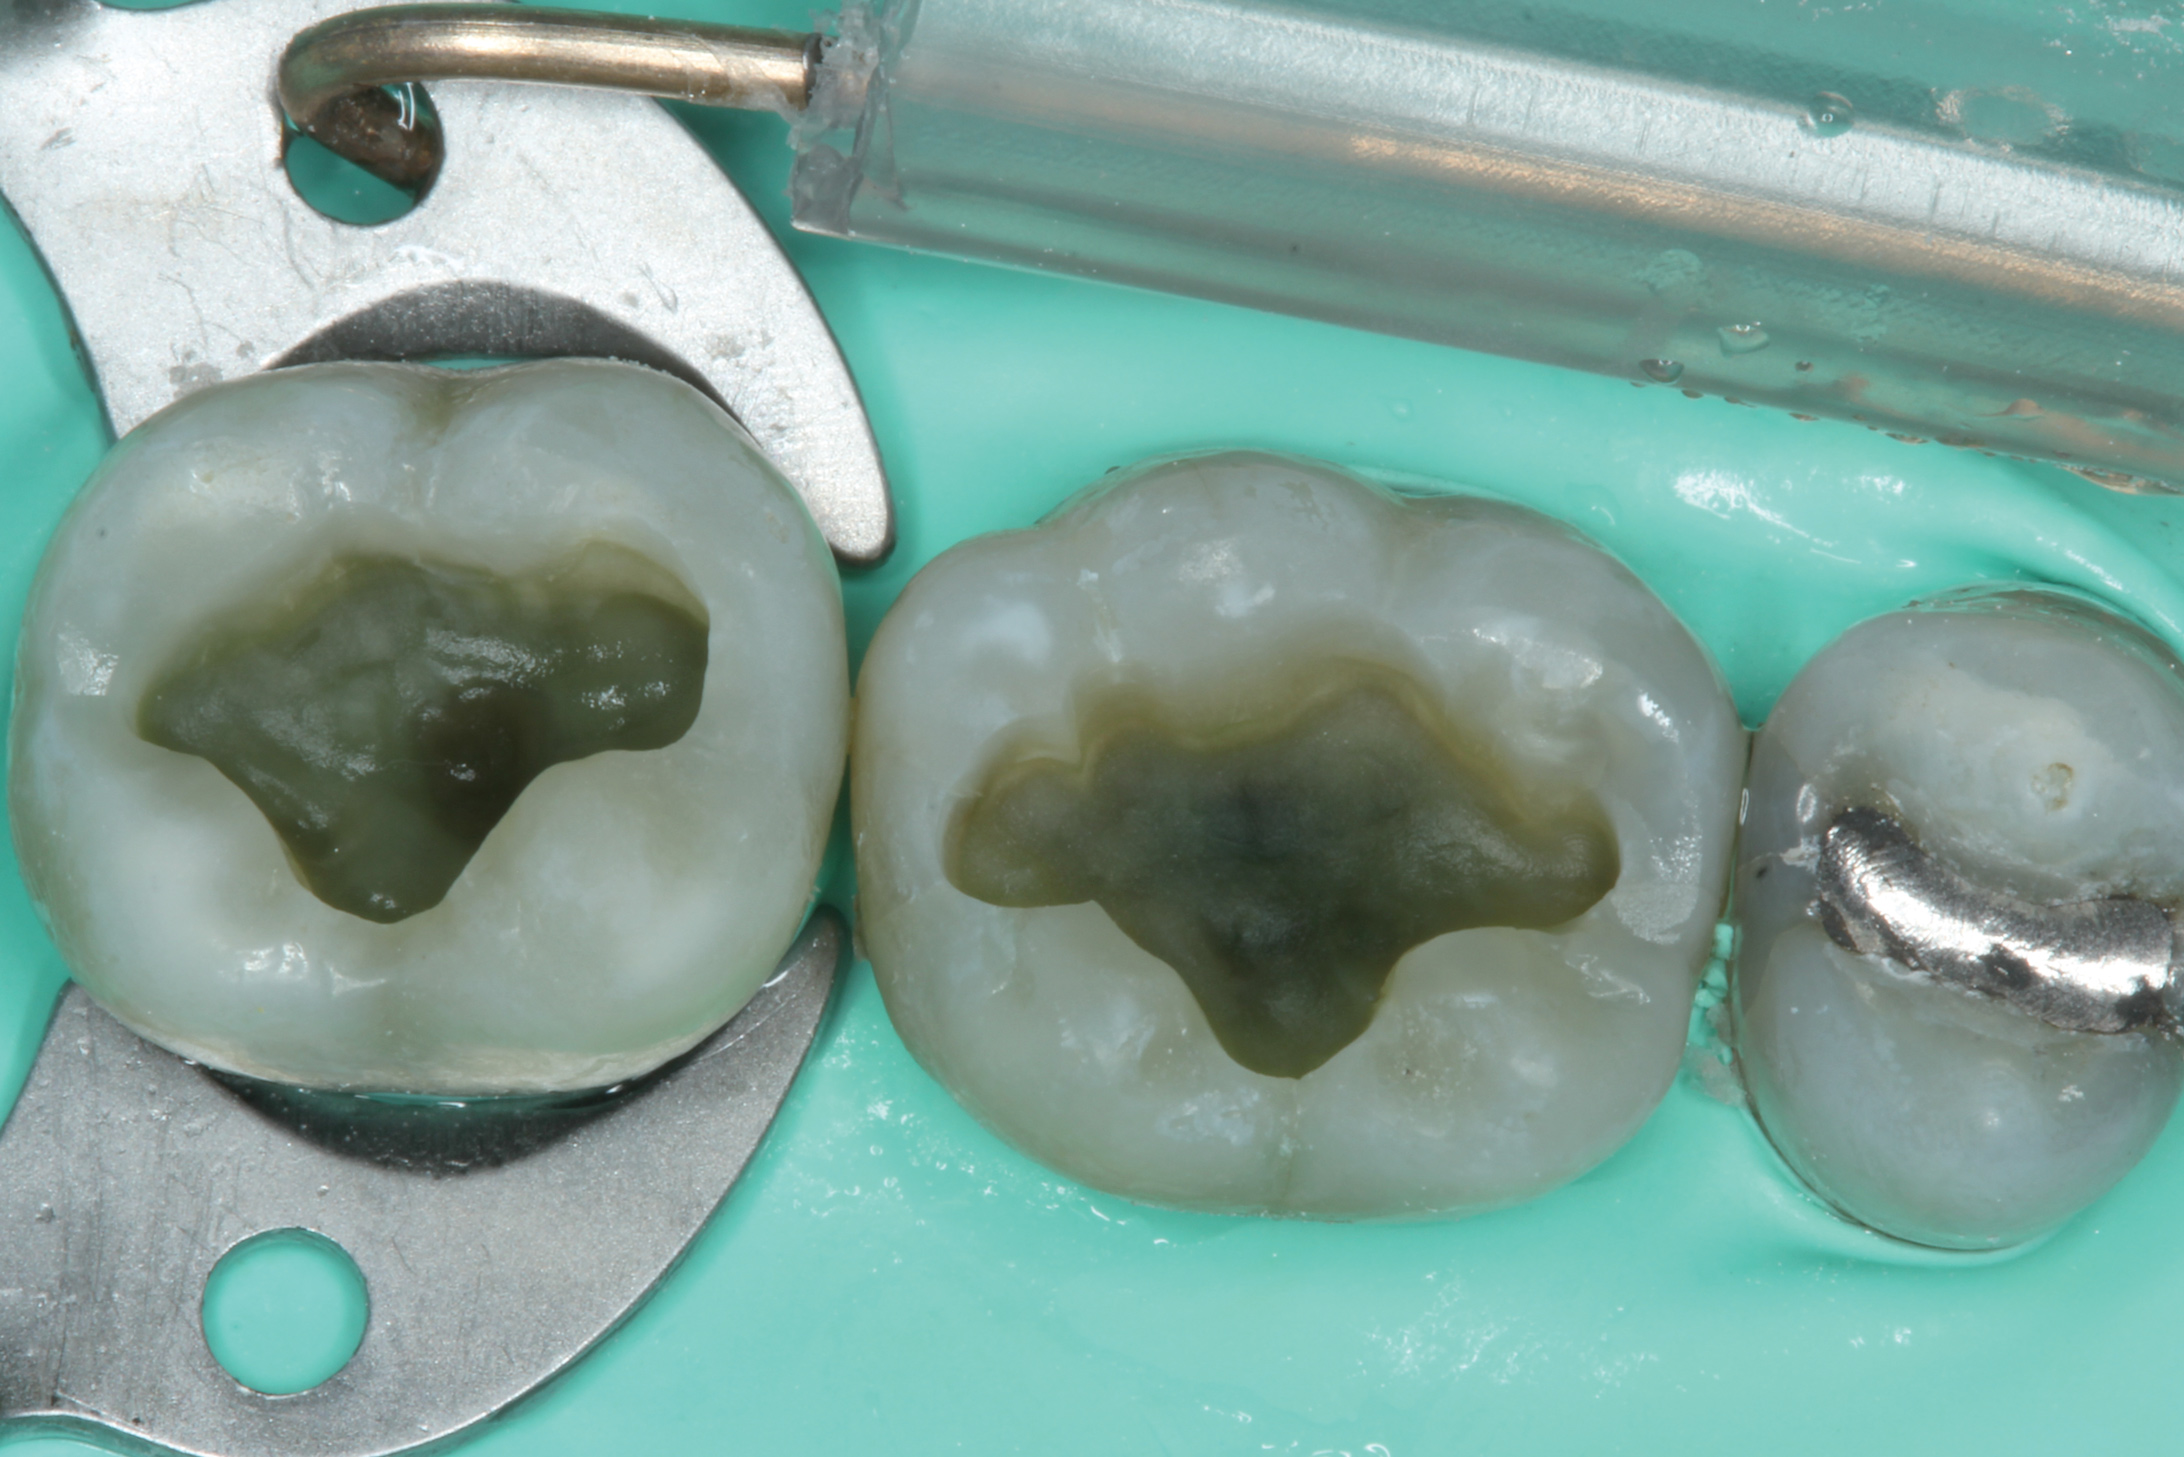

With these limitations acknowledged, visual inspection of tooth preparations after air abrasion reveals that this modality is effective in removing remnant restorative materials, stains, and temporary cement, leaving a clean, matte surface for bonding (Figure 11 through Figure 14). Air abrasion also can smooth the internal aspects of a cavity preparation to help enable better adaptation of the restorative material (Figure 15 and Figure 16). The technique-sensitive nature of adhesive bonding may justify this extra procedure to ensure a clean, smooth preparation.

Fig 15. Cavity preparation prior to air abrasion (Fig 15) and after air abrasion (Fig 16).

Figure 15

Fig 16. Cavity preparation prior to air abrasion (Fig 15) and after air abrasion (Fig 16).

Figure 16